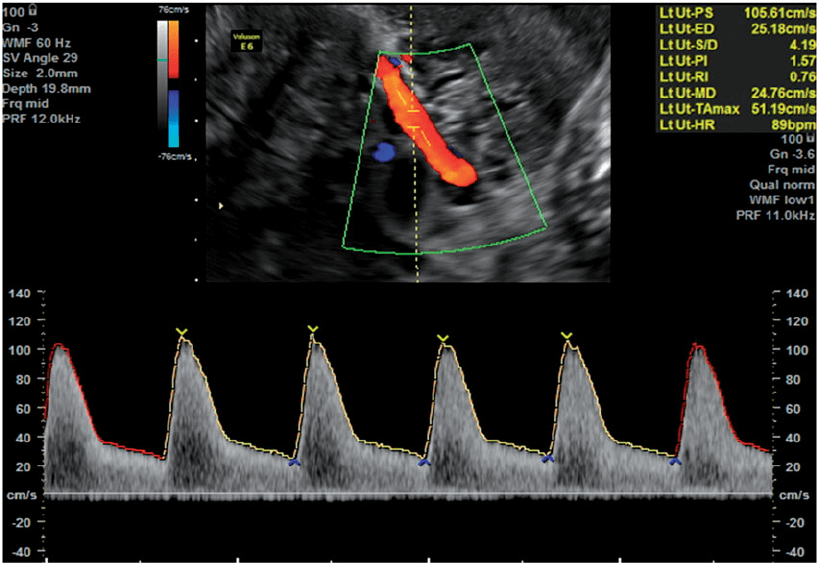

- Uterine Artery Doppler measurement.